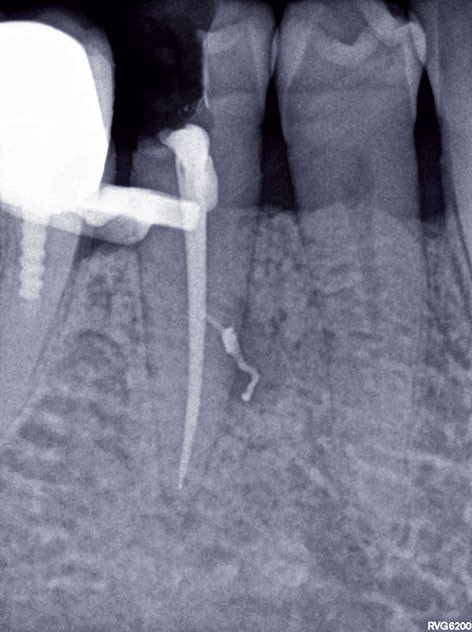

7, 8, 9. L’obturation canalaire à la gutta percha est partiellement éliminée avec le foret universel et le canal radiculaire est mis en forme avec le foret de calibrage 3M™ RelyX™ Fiber Post de 1,1 mm de diamètre. L’élimination totale de la gutta percha sur la longueur désirée est vérifiée à l’aide d’une radiographie rétro-alvéolaire. Un insert à ultrason est utilisé, son action mécanique permettant de finir de nettoyer le système canalaire et d’éliminer les résidus de ciment endodontique pouvant encore être présents.